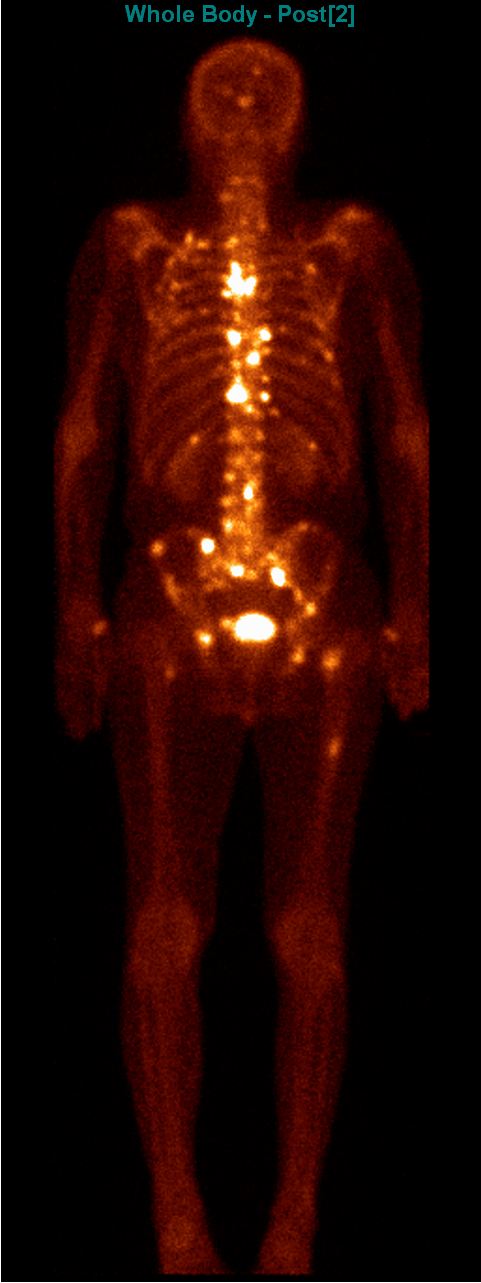

Among the general characteristics of isotope examinations, besides the ability to gain functional information, it is important to mention that – derived from the tracer principle – the examinations are highly sensitive, so the pathological processes can be detected at an early stage. SPECT is able to detect nano-molar radiotracer concentrations, while PET picks up signals coming from pico-molar radiopharmaceutical quantities. The higher sensitivity is due to the fact that functional alterations of metabolism usually precede detectable morphological changes of the tissues, thus functional studies allow earlier and more precise diagnostics. Another aspect of higher sensitivity is that in an optimal scenario, the biologic contrast between normal and pathologic function is very high. Therefore, signal intensity of a normal tissue process will be much lower than that of a pathologic one, making them easily distinguishable on the image. (Figure 2.)

Test iframe

2. FDG PET Maximum Intensity Projection (MIP) image. There is a large biological contrast between the normal and the pathologic tissues. Right sided breast cancer, ipsilateral metastatic lymph nodes and multiplex metastases in the lung. Physiologically elevated FDG uptake is seen in the brain, salivary glands, tonsils, liver and the spleen as well as in the bone marrow and at certain segments of the intestines. Also, there is increased FDG activity in the kidneys and the urinary bladder due to excretion.